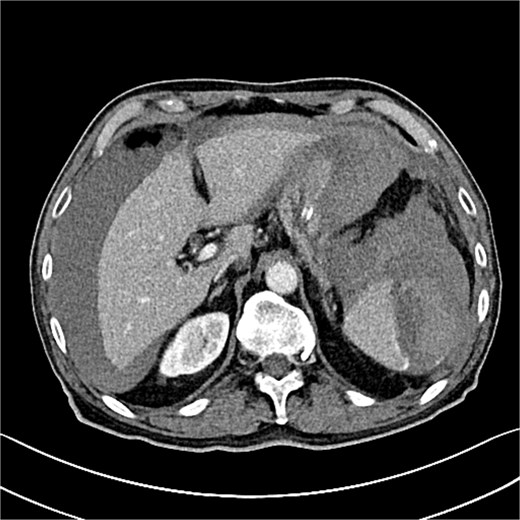

Seven hours post-procedure, the patient presented to the emergency department with abdominal pain, syncope, diaphoresis, and bloating. His blood pressure was 80/50 mmHg, and his heart rate was 120 beats per minute. Abdominal examination revealed tenderness in the left hypochondrium, and his hemoglobin level was 6.2 g/dl with a hematocrit of 38%. A contrast-enhanced abdominal computed tomography (CT) scan showed a ruptured spleen with a 7-cm parenchymal hematoma, a significant blood halo surrounding the liver, and a large blood accumulation of 15 × 12 cm in the pelvis (Figs 1 and 2).

The CT scan reveals splenic hematoma with a significant blood halo surrounding the liver.